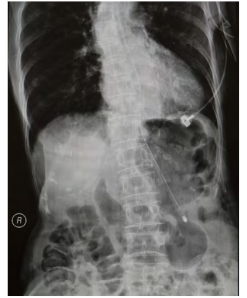

2. 用X线片确认放置位置(胃[NG]或小肠[NJ]喂养是可以接受的)。

• 胸部X光片显示插管位置